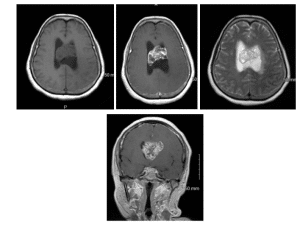

Imaging: A non-contrast computed tomography (CT) identified an intraventricular soft tissue mass centered at the anterior aspect of the septum pellucidum covering the foramen of Monro bilaterally and extending to the body of the corpus callosum (Figure 1).

Figure 1: Non-contrast axial CT images of 62 y/o female with intraventricular mass at the anterior aspect of the septum pellucidum covering the foramen of Monro bilaterally and extended to the body of the corpus callosum